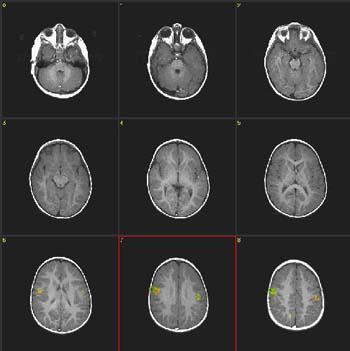

Case 4

| Patient | Normal 18 month-old-boy | ||||||

| Paradigm #1: | ON: Presentation of mother's voice, pre-recorded, using familiar words OFF: Nothing. Patient sedated with chloral hydrate | ||||||

| Statistics |

| ||||||

| Graphic of Time Course | 6 epochs starting in OFF![]() | ||||||

| Image | ![]() | ||||||

| Activation | There is bilateral activation on the parasagital aspects of the frontal lobes, greater on the right. The primary auditory area is activated on the left. Scattered activation is also present on the right parietal lobe. There is bilateral activation of the cuneus and precuneus wider on the left. | ||||||

| Paradigm #2: | ON: Presentation of flashing lights, 8 Hz OFF: Nothing. Patient sedated with chloral hydrate | ||||||

| Image | ON-OFF | ||||||

| Activation | There is bilateral activation of the motor strip, and "deactivation" of anterolateral region of the calcarine fissure (periferal V1) as seen in the case No. 3. The location of this response is expected since the type of stimulus used here causes greater activation of the peripheral retina than of the fovea. The activation of the motor areas through visual stimulus is similar to the obtained with mother's voice in case No. 1. |